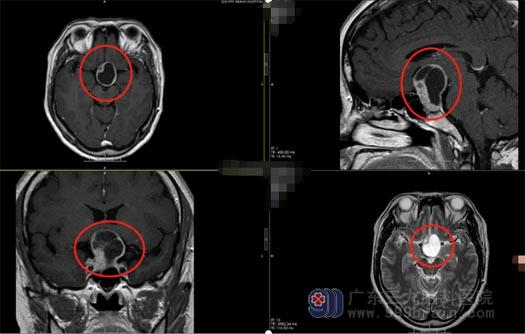

六个月前,谭女士突然出现了左眼视力下降的问题,因症状不是很严重,所以并未在意,直到近几天,除了视力下降还突然出现了看东西变窄、头晕的情况,谭女士及其家人这才意识到问题的严重性,“这样下去会不会瞎呀”,他们带着恐惧和疑问到当地医院就诊,最后经头颅MR确诊不是眼睛的问题,而是脑袋里面长了肿瘤。

为求进一步治疗,谭女士及其家人来到三九脑科医院外五科,鲁明副院长进行了仔细的病史了解及影像查阅,初步考虑是垂体瘤,并明确告知不用开颅就可以把肿瘤切除。

▲术前